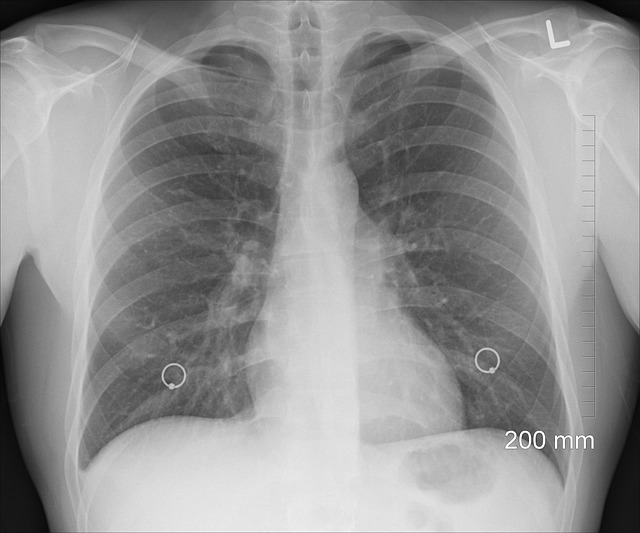

- 소아청소년과에 방문했을 때 의사 선생님이 진찰을 위해서 가슴 쪽에 청진기를 대는 것은 폐소리를 듣기 위함인데요. 일반 감기랑 바이러스성 폐렴인 경우는 폐소리가 다르고, 좋지 않은 소리가 들릴 경우 엑스레이 촬영을 하게 됩니다. 엑스레이 촬영결과는 대부분 찍자마자 바로 확인이 가능합니다. 바로 이런 사진을 보여주시면서 설명을 해주시는데요.

[폐 음영사진을 보면, 한쪽이든, 양쪽이든 폐 쪽이 깨끗하지 않고, 음영된 부분크기에 따라 심한 정도인지를 알려주십니다.]